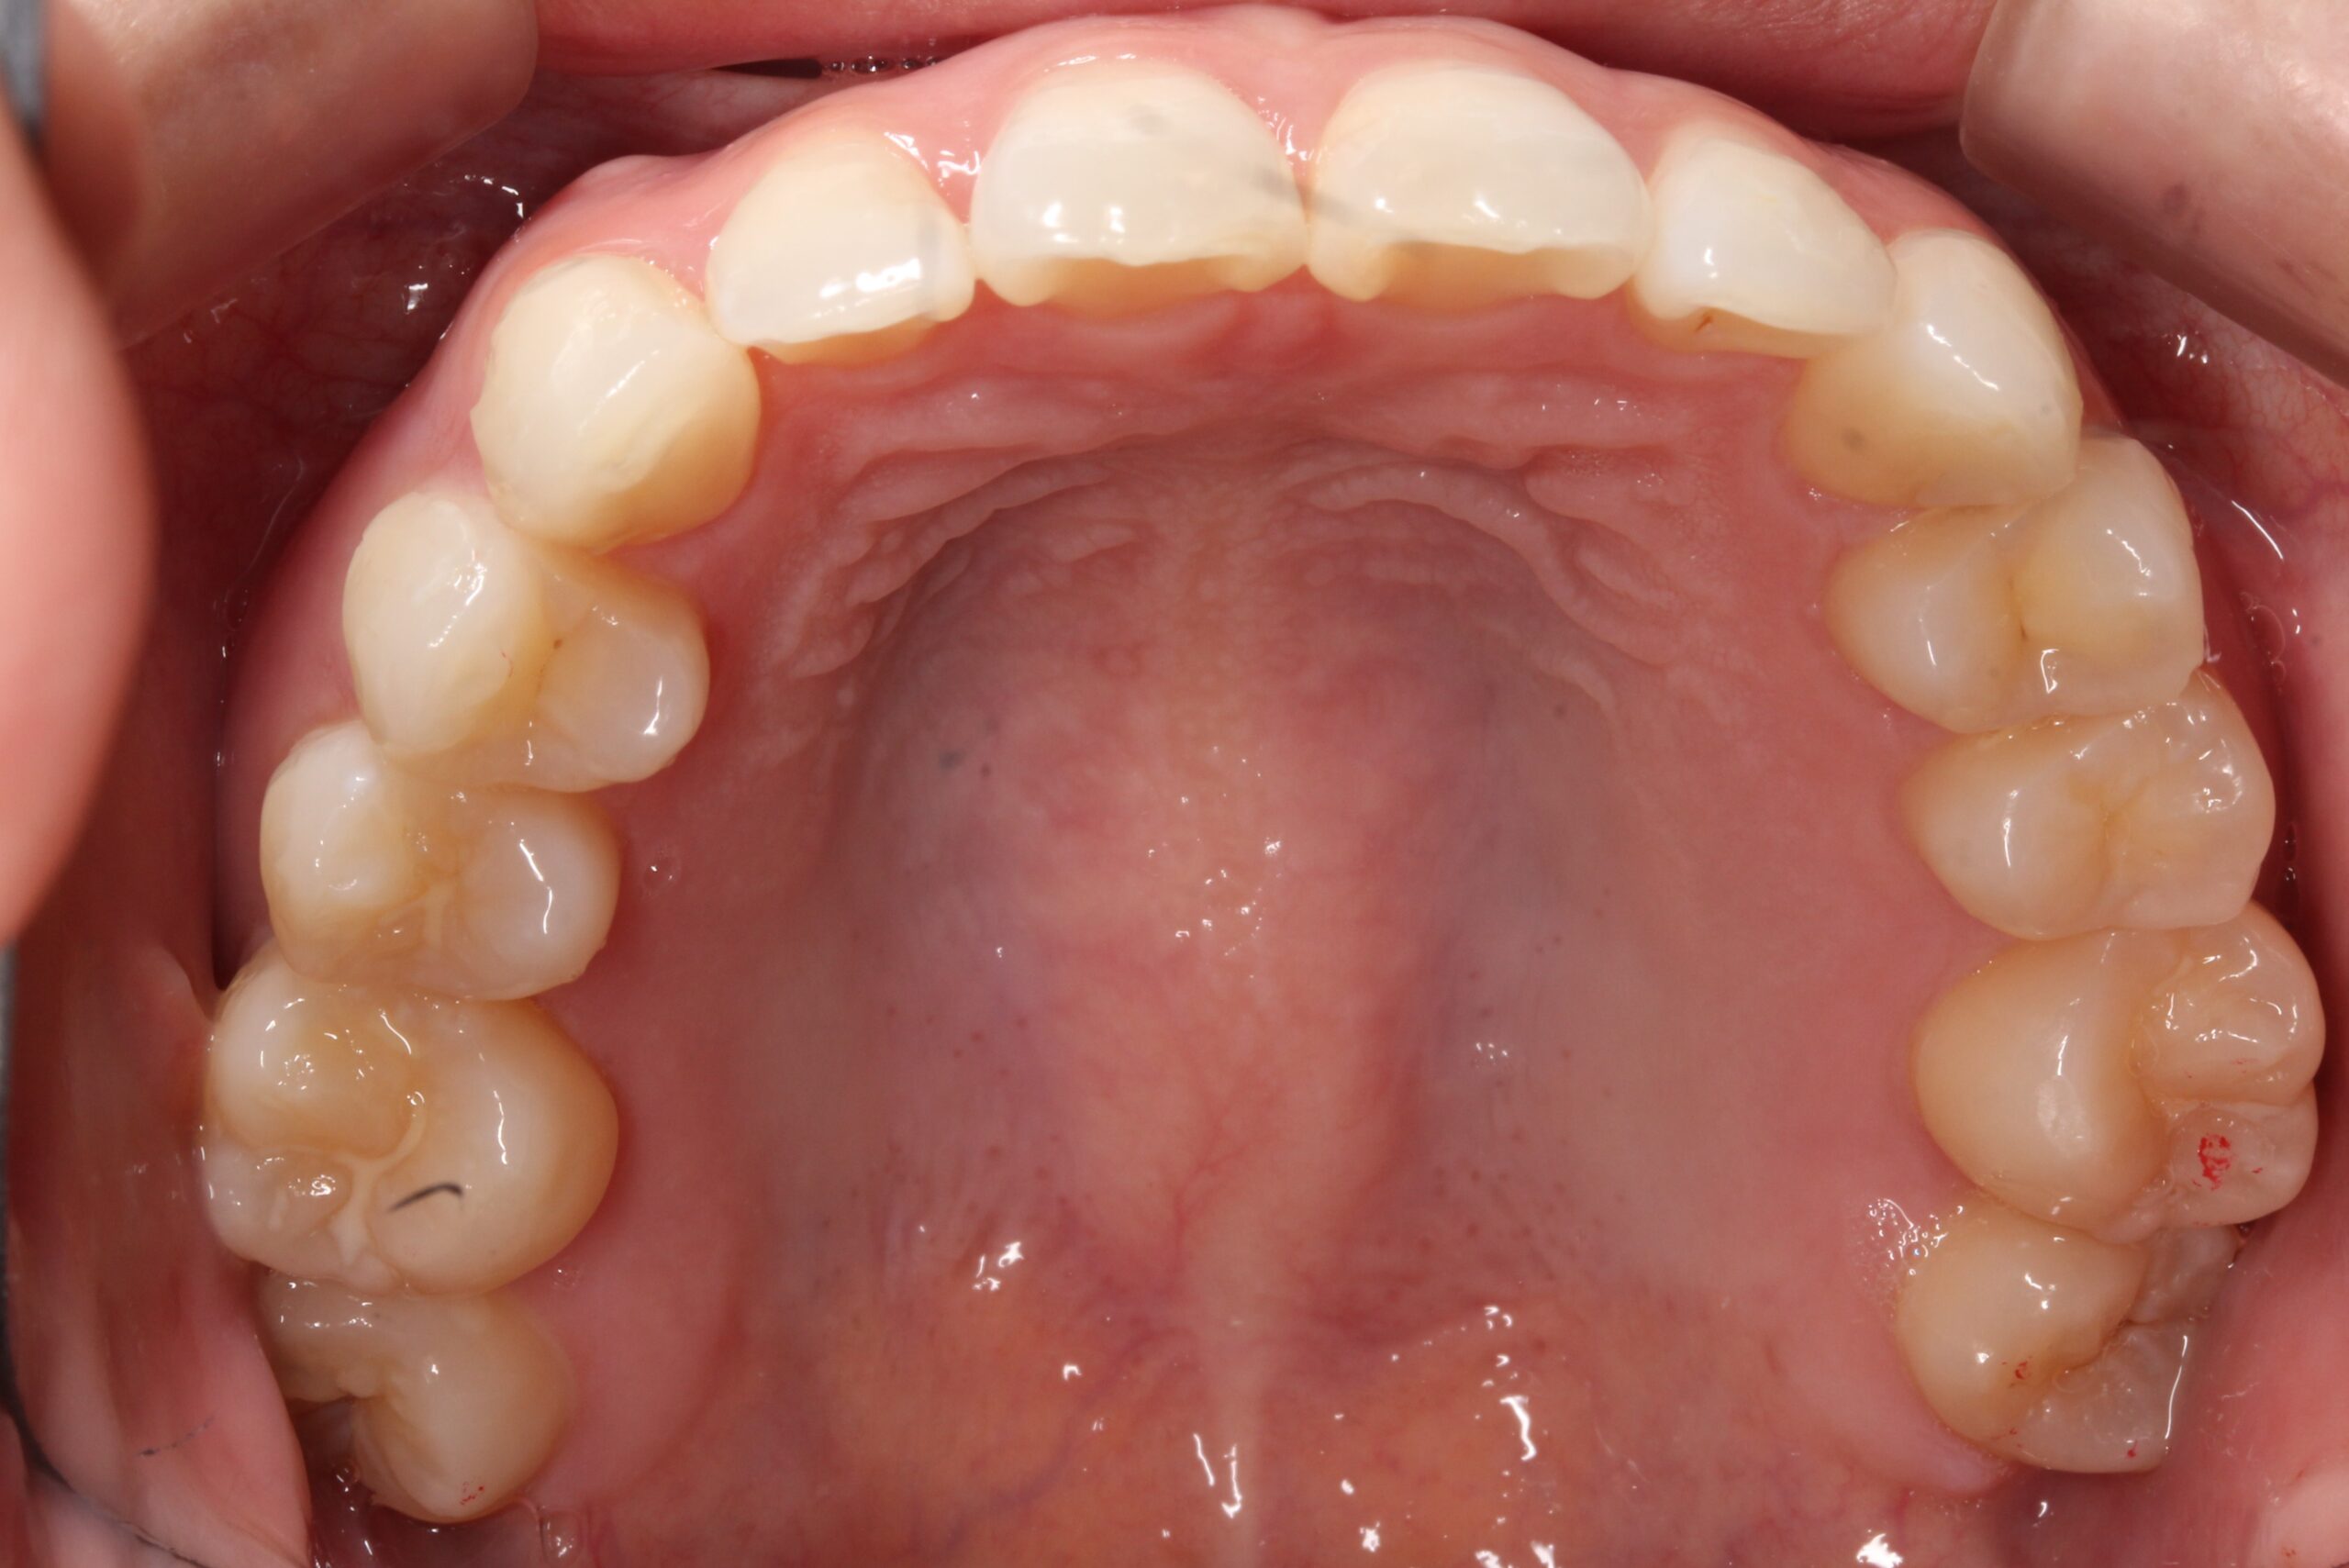

矯正術前:下顎

矯正術後:下顎